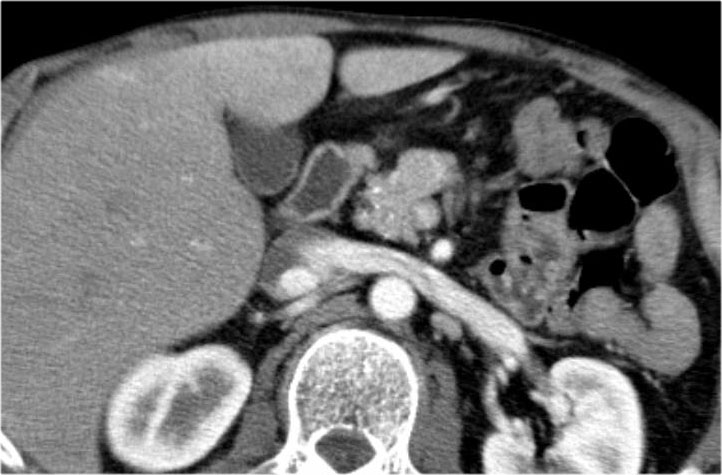

Bệnh nhân này bị viêm tụy mạn tính.

Lưu ý các vôi hóa ở đầu tụy (mũi tên cong).

Có nhiều nang giả tụy lan dài vào tận trung thất, gây chèn ép tim (mũi tên đỏ).